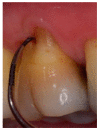

Various classification systems have been proposed to describe furcation lesions and Glickman's classification for many years seems to have been the most widely utilized in the sole clinical diagnosis with no reference to the prognostic value of the lesion itself. This article reviews the previous classification systems and proposes a new method to classify furcation lesions based on the position of the gingival margin and its relationship with the furcation area (clinically exposed/non-exposed furcation area) providing significant aid for a better understanding of furcation involvements and increases the prognostic value of treatments in the long term.